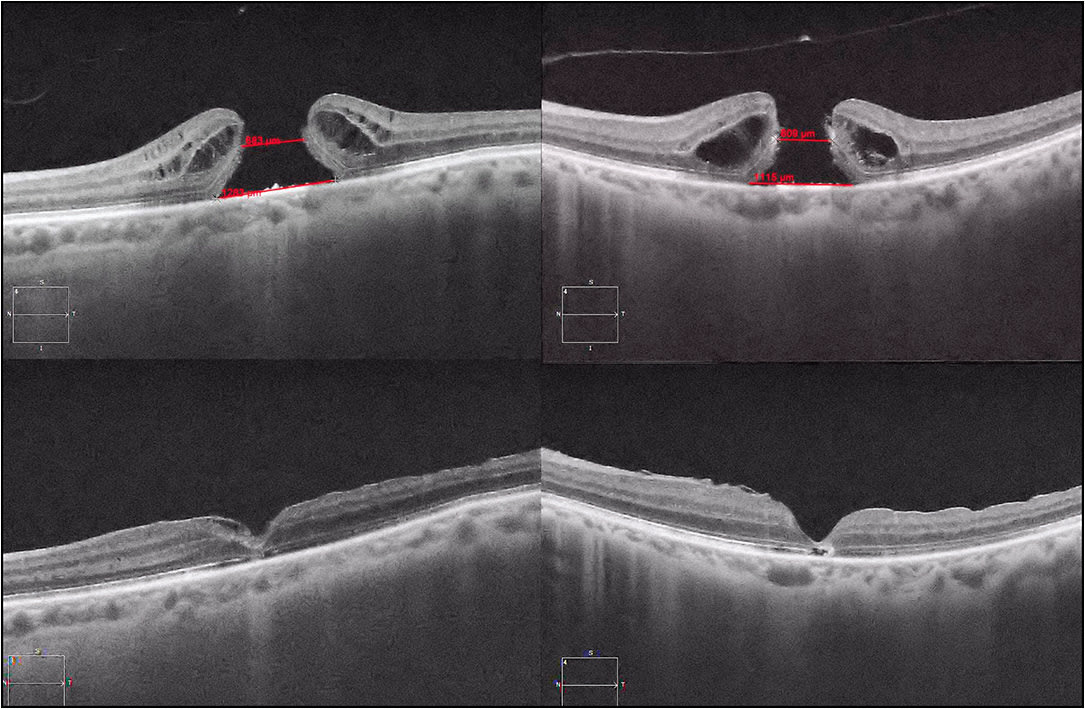

Since larger MH basal diameter size is a predictor of surgical success that is independent of MH MLD, we should consider both the MLD and the base diameter when evaluating an MH. We could consider defining “giant” MHs as all large MHs (MLD >400 µm) with a base diameter >700 µm (a base diameter between the 500-µm 0% and 1,000-µm 19.1% failure rates in the above-cited study), perhaps guiding us to choose surgery other than a standard ILM peel in this patient cohort (Figure 1).45